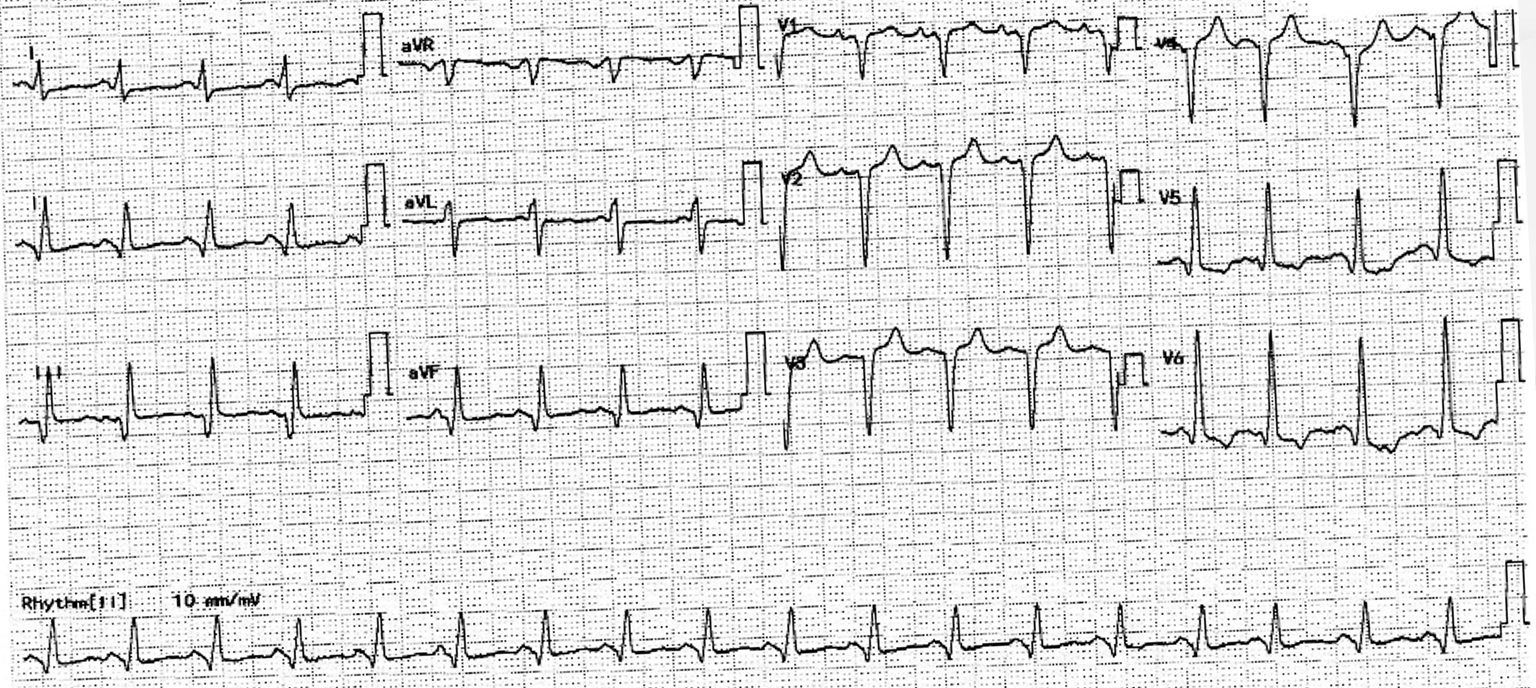

Relevant Test Results Prior to Catheterization

Electrocardiogram showed poor R wave progression and inferior leads Q wave. Cardiac enzymes were elevated. Echocardiogram showed severely impaired LVEF at 20% with multiple regional wall hypokinesia.